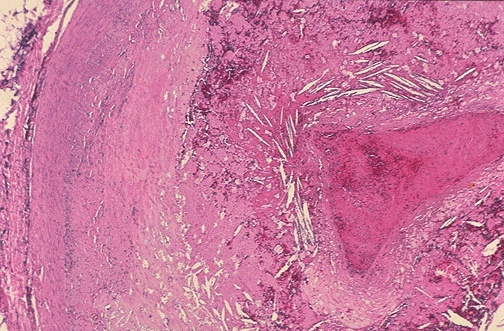

Image 2.2

This is the microscopic appearance of his left anterior descending coronary artery.